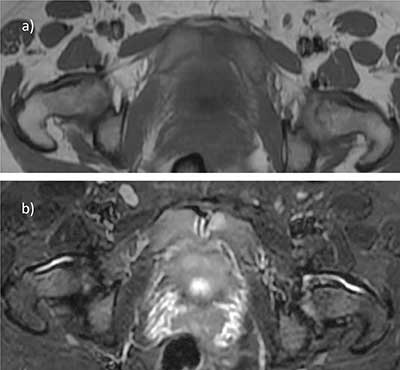

Figure 1

Transient osteoporosis of the right hip; MRI shows diffuse bone marrow edema of the femoral head extending in the femoral neck, with no fracture or osteonecrosis line. T1 spin echo (SE) coronal image a) Shows diffuse low signal of the whole femoral head. SE T2 b) and STIR c) Coronal images show heterogeneously high signal in the same area, with moderate joint effusion.